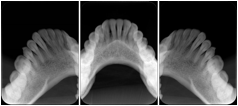

Intra-oral radiography typically involves acquisition of multiple images of various parts of the dentition. Many digital radiographic systems offer customized templates that are used for displaying the images in a study on the screen. These templates may also be referred to as mounts or view sets. The Structured Display Object represents a standard method of encoding and exchanging the layout and intended display of Structured Displays. A structured display object created in this manner could be stored with a study and exchanged with images to allow for complete reproduction of the original exam.

1. A patient visits a General Dentist where a Full Mouth Series Exam with 18 images is acquired. The dentist observes severe bone loss and refers the patient to a Periodontist. The 18 images from the Full Mouth Series along with a Structured Display are copied to a DICOM Interchange CD and sent with the patient to see the specialist. The Periodontist uses the CD to open the exam in his Dental Radiographic Software and consults via phone with the General Dentist. Both are able to observe the same exam showing the images on each user's display using the exact same layout.

Intra-oral Full Mouth Series Structured Display

Figure OO-1. Intra-oral Full Mouth Series Structured Display